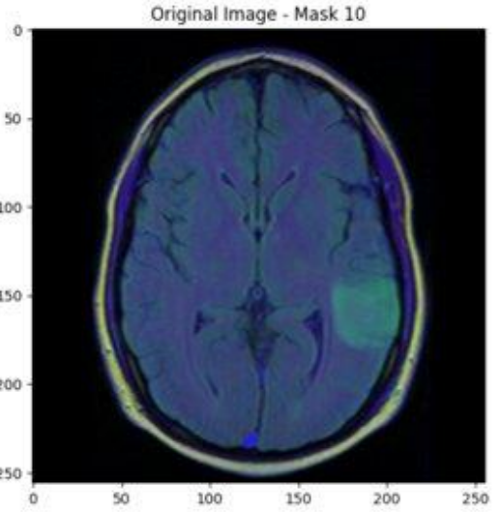

One immediate use of ReX is in the field of medical imaging. When a patient with a suspected brain tumour gets an MRI, an AI system on the other side will automatically classify the scan as either containing a tumour or not. If the system believes the scan has a tumour, then it goes immediately to the physician. If not, the scan will still go to the physician, but maybe it will only get to them in a couple days.

With ReX, the AI system can say “the tumour is over here!” which helps the physician diagnose much faster. ReX can also explain the absence of a tumour in an image. Since tumours tend to show up as a different colour from healthy tissue, ReX can return a grid of healthy tissue-coloured pixels and say, I know that all this tissue is healthy, and no tumour can fit in between all this healthy tissue. Hence there cannot be a tumour in this brain scan. If the physician disagrees, they can tell the AI to check closer in suspicious areas, supporting a dialogue between the physician and the AI system. (You can read more about this work in this 2023 paper by Chockler and her colleagues.)